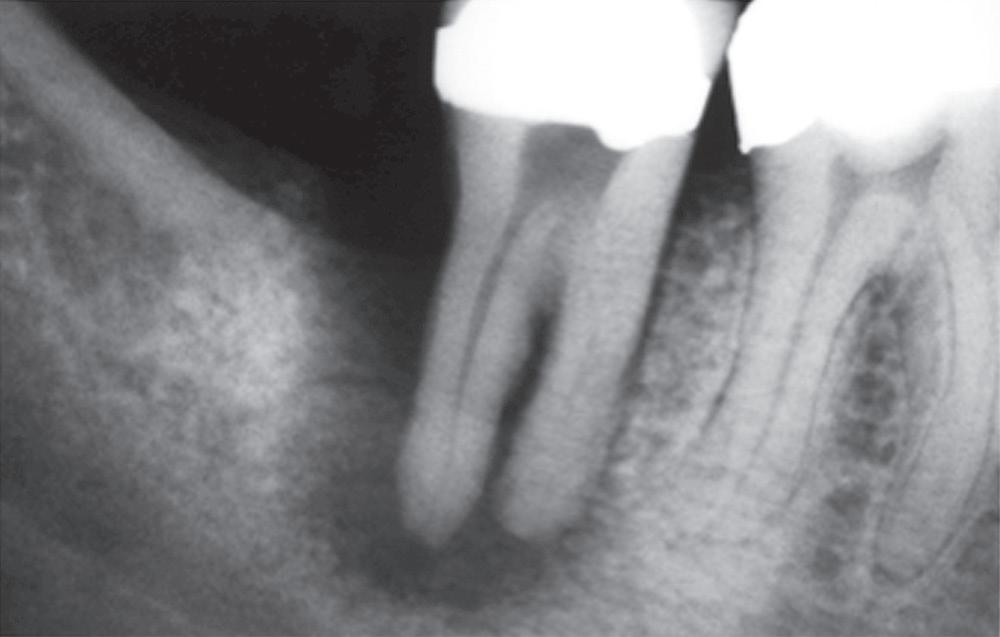

a result of traumatic injuries, a substantial increase in mineralization may occur in the tooth or teeth that were traumatized. Increased areas of mineralization, commonly known as pulp stones , are also associated with caries or deep restorations. Excessive pulp stones have also been associated with cardiovascular diseases, 51 and with intake of statin medications. 52 Increased mineralization of the pulp, even when obliterating the entire canal space ( Fig. 1.18 ), in the absence of symptoms or apical pathosis, is not considered pathologic. However, if pulpal disease arises in these conditions, root canal treatment may become very challenging.